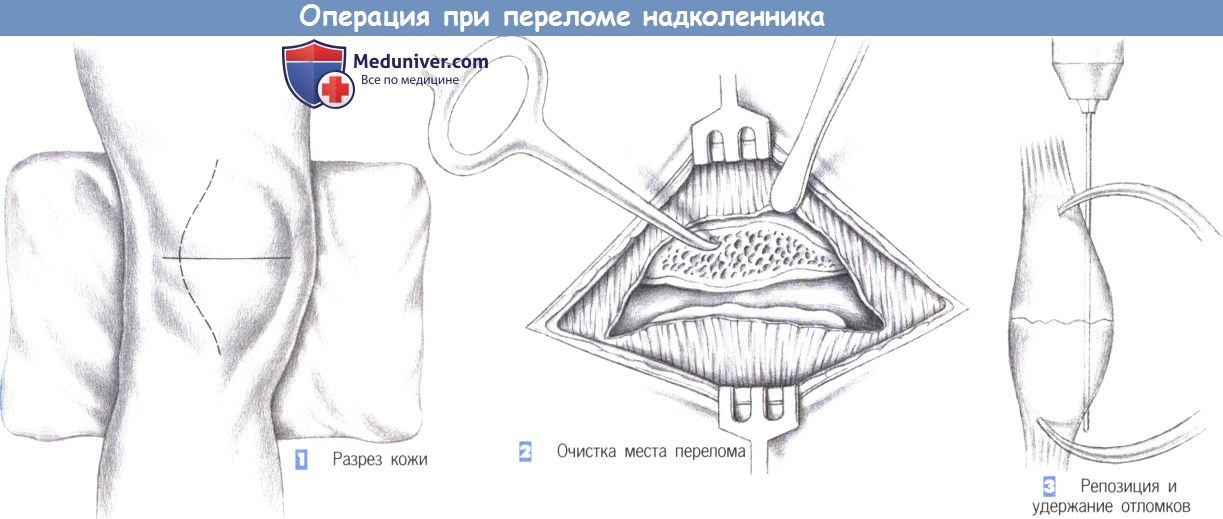

Как фиксируют надколенник? Вариант остеосинтеза определяется типом перелома. При поперечном переломе сопоставить и скрепить отломки можно с посощью специальной медицинской проволоки (серкляжа) и спиц. Такую операцию называют именем ее изобретателя – Вебера.

Оперативное лечение показано при переломах надколенника с расхождением отломков более чем на полсантиметра. При этом чаще всего пользуются методом Берже-Шультце, при котором после разреза мягких тканей удаляют сгустки крови, сближают отломки, на разорванные боковые связки накладывают швы. После этого мягкие ткани надколенника вокруг него прошивают нитями (одна нить сверху, другая снизу), захватывающими глубокие ткани. Срок иммобилизации после такой операции — около месяца, после чего назначают физиотерапевтические процедуры и массаж.

Процедура проводится под локо-региональным или общим наркозом с пневматическим жгутом. Установка должна обеспечивать полную мобилизацию колена. Вырезание кожи — это внутренний парамедиан, иногда управляемый раной. Внутренняя артротомия является систематической для контроля суставов и выявления остеохондральных повреждений надколенника и хряща.

Рисунок 11: разрез в байонетке с поперечной раной. Артротомия должна быть как можно короче, чтобы сохранить васкуляризацию надколенника, но должно быть возможно проверить анатомическое сокращение перелома, что является приоритетом остеосинтеза. Рисунок 12: Поперечный перелом: рабочий вид.

Рисунок 13: Интраоперационный редукционный контроль. Используются различные средства остеосинтеза, которые должны всегда обеспечивать достаточную стабильность сборки для ранней мобилизации. Это метод выбора для поперечных переломов. Двадцать параллельных штифтов вводятся на передней трети надколенника после восстановления. Остаток сделан из проволоки, что позволяет динамически сжимать фокус переломы. В начале эксперимента принято считать, что металл остается слишком далеко от коленной чашечки до верхнего и нижнего полюсов, что ставит под угрозу сжатие камина.

Лечение перелома надколенника зависит от смещения отломков. При переломе без смещения возможно лечение гипсовой повязкой, при малейшем смещении — необходима операция на коленной чашечке. Смещение отломков составной поверхности надколенника должно быть обязательно устранено на операции, поскольку именно суставная поверхность надколенника скользит по мыщелкам бедренной кости при разгибании ноги в коленном суставе. При наличии смещения либо будет вообще отсутствовать разгибание, либо будет формироваться артроз бедренно-надколенникового сочленения. Отломки при переломе надколенника можно фиксировать винтами, спицами, проволокой.

Наиболее распространённый способ фиксации – это остеосинтез по Веберу, хирургу, который придумал эту операцию. При этой операции для фиксации используются спицы и проволока (продемонстрировано на схеме ниже).